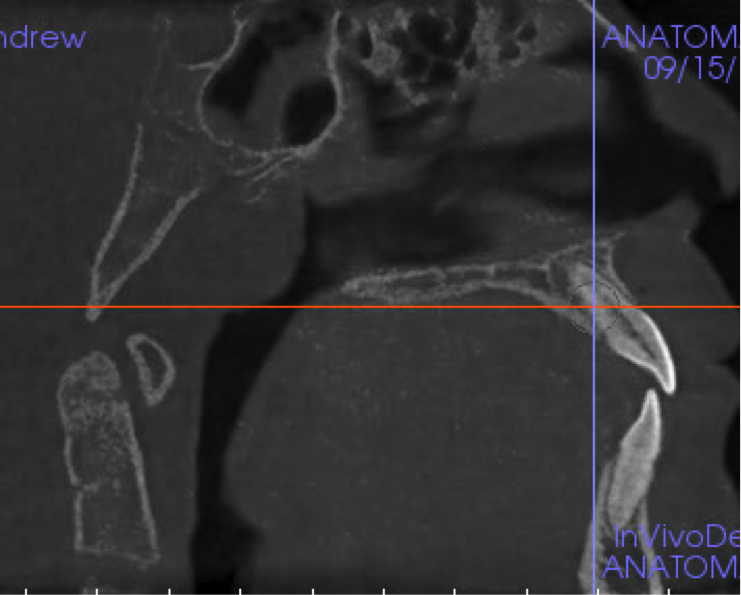

There is a documented link between radiologic image quality and diagnostic efficiency.6 In other words, a reduction in scan quality may obscure diagnostic information and compromise diagnosis. Patient motion during the scan acquisition and other image artifacts are the most important factors affecting image quality in CBCT studies. Patient motion is more likely to be seen in scans of either older individuals or children. The motion artifact can be recognized by the double margin it creates in the osseous boundaries, such as the maxillary and mandibular cortices. To limit motion artifacts, detailed patient instructions may be helpful as well as strict adherence to the manufacturer’s recommendations for scan acquisition (Figure 2). After the acquisition of a scan, the clinician should quickly review the image data for possible motion artifacts and retake the san if necessary.

(2.) CBCT orthogonal sections showing severe patient motion. Note the double margin of the maxilla and mandible, especially in the sagittal section (upper left). This scan has to be retaken.

Figure 2